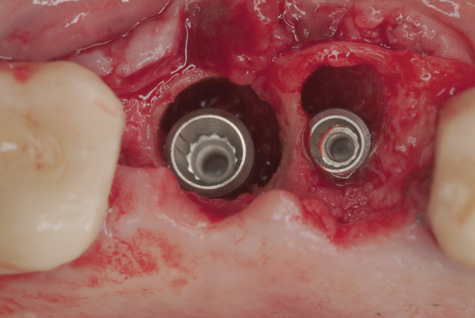

Because the osteotomy created by the trephine is wider than the originally placed implant, it may be challenging to immediately replace this implant unless there is sufficient apical bone available for implant stabilization. For some cases, a wider implant can be placed, but the physiologic rules requiring 1.5 to 2.0 mm for tooth/implant or 3.0 mm for implant/implant spacing,2 as well as other established esthetic criteria, must be respected. For example, a clinical examination revealed a fractured implant in the position of tooth No. 14 along with a fracture to tooth No. 13 (Figure 4). After trephine removal of the fractured implant and extraction of the fractured bicuspid, two implants were placed (Astra Tech, Dentsply Sirona), utilizing apical and axial bone in the apical third of the osteotomy and alveolus to stabilize both fixtures (Figure 5). When this cannot be performed, a staged approach should be employed wherein the site is augmented to facilitate implant placement 4 to 6 months after explantation and grafting.

(4.) The implant in the molar position was relatively narrow and failed biomechanically. It was removed with a trephine, and the adjacent fractured bicuspid was also extracted to accommodate an implant. Because sufficient apical bone was present, a wider implant was placed in the molar position. Bone augmentation was performed around both implants.

Figure 4

(5.) The implant in the molar position was relatively narrow and failed biomechanically. It was removed with a trephine, and the adjacent fractured bicuspid was also extracted to accommodate an implant. Because sufficient apical bone was present, a wider implant was placed in the molar position. Bone augmentation was performed around both implants.

Figure 5